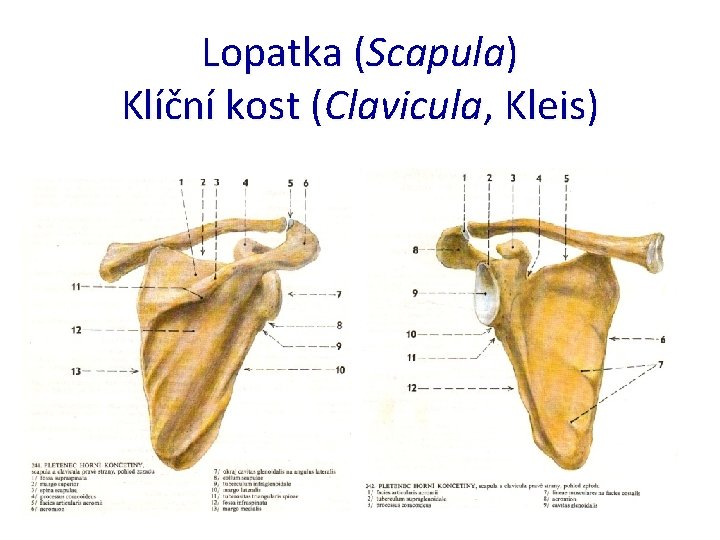

Lopatka (Scapula) Klíční kost (Clavicula, Kleis)